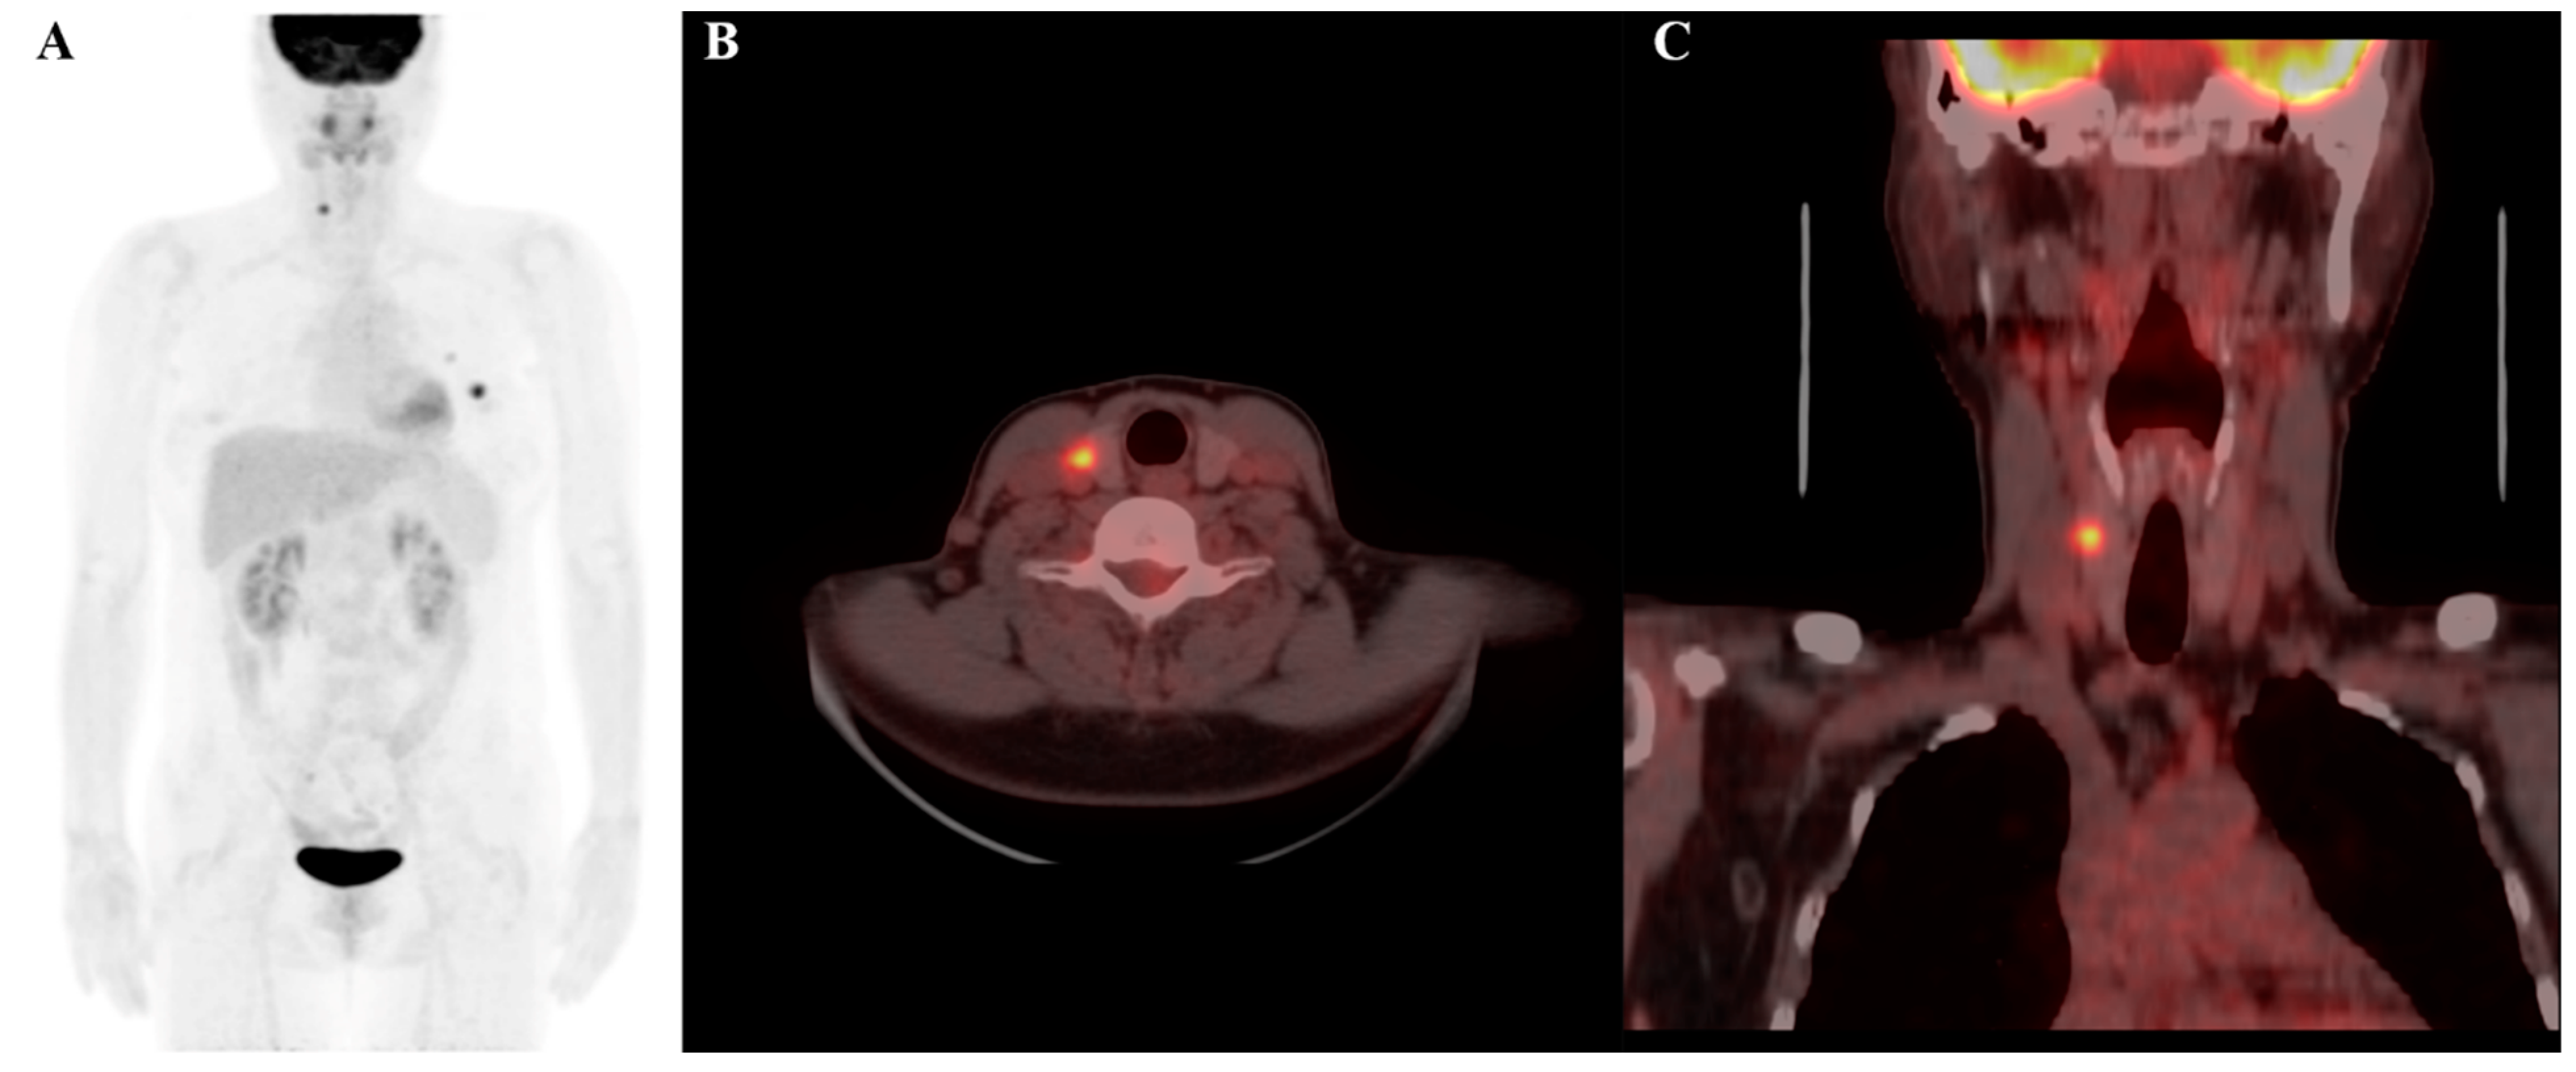

Figure 5.

F-18 FDG PET/CT image of a 56-year-old female patient, showing a thyroid incidentaloma located in the right lobe of the thyroid gland: (A) maximum intensity projection (MIP); (B) axial PET/CT image; and (C) coronal PET/CT image. The lesion exhibits elevated FDG uptake, with a maximum standardized uptake value (SUVmax) of 7.3. Radiomic analysis reveals a log-sigma-2-0-mm-3D_glszm_SmallAreaEmphasis value of 0.734 (relatively high) and a wavelet-HLH_gldm_LargeDependenceLowGrayLevelEmphasis value of 4.440 (relatively low). The final diagnosis confirmed that the nodule was malignant.